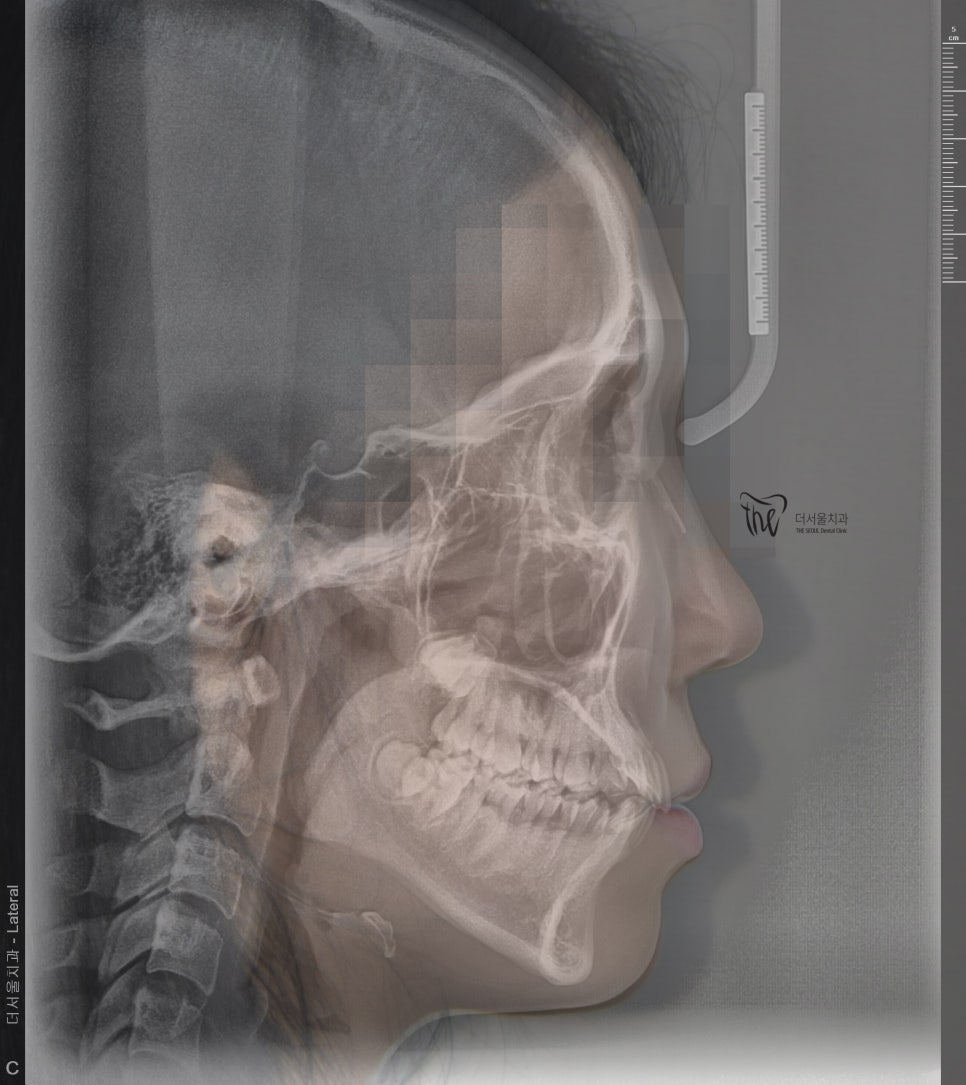

이 환자는, 10대입니다.

아직 성장기에 있으며 앞서 말씀드린 것 처럼

뼈가 다 굳지 않았을 때 교정치료를 하는 것이

더 빠르고 정확하게 치아이동이 가능하다는 것을

설명드렸던 적이 있었죠.

인비절라인 클린첵 시뮬레이션을 돌려봤으며

크게 2가지 포인트를 보면 되겠습니다.

- 전치부, 총생 개선

- 반대교합, 어금니 위치 이동에 따른 교합조정